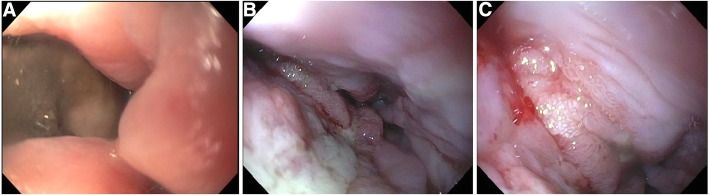

В течение месяца до обращения у него были эпизоды тошноты, рвоты и дисфагии, за последний год он потерял 40 кг. При осмотре зафиксирована тахикардия (110 ударов в минуту), гипотония (86/68 мм рт. ст.) и тахипноэ (до 40 вдохов в минуту), а также болезненность в левой половине грудной клетки. РКТ органов грудной клетки выявила перфорацию пищевода, левосторонний гидропневмоторакс (рис. 1 — A) и утолщение пилорического отдела желудка (рис. 1 — B).

Рисунок 1 [2].

Рисунок 3. Серия эндоскопическихобследований перфорации пищевода (эндофото) [2]А. Первая ЭГДС: обширный дефект пищеводной стенки, визуализируются средостение и перикард.

B. ЭГДС после удаления пищеводного стента: наблюдается заживление дефекта с образованием грануляционной ткани.

С. Полное заживление перфорации.